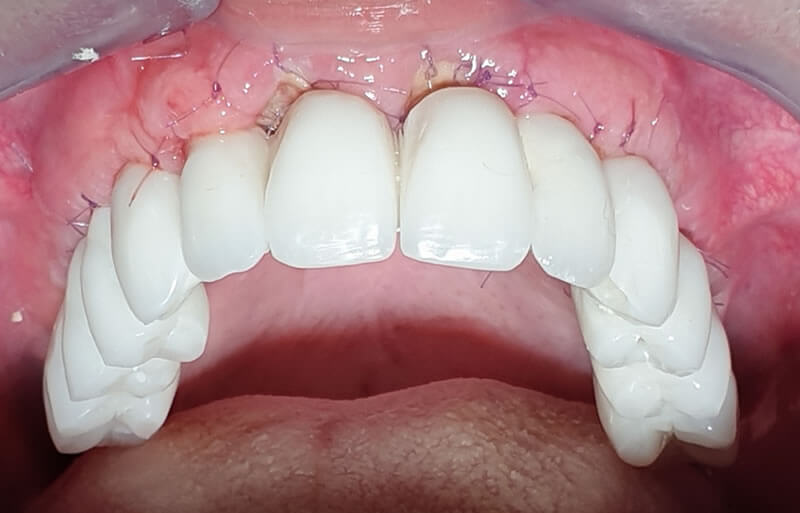

Même cas clinique « GOLD STANDARD MCI » terminé : Bridge implanto-porté sans extension (ALL ON 8). Version définitive des bridges avec un cosmétique en céramique (ALL ON 8/8).

LE REMPLACEMENT DES BRIDGES RÉSILIENTS PROTOTYPES PAR LES BRIDGES DÉFINITIFS EN CÉRAMIQUE A ÉTÉ EFFECTUÉ 6 MOIS PLUS TARD